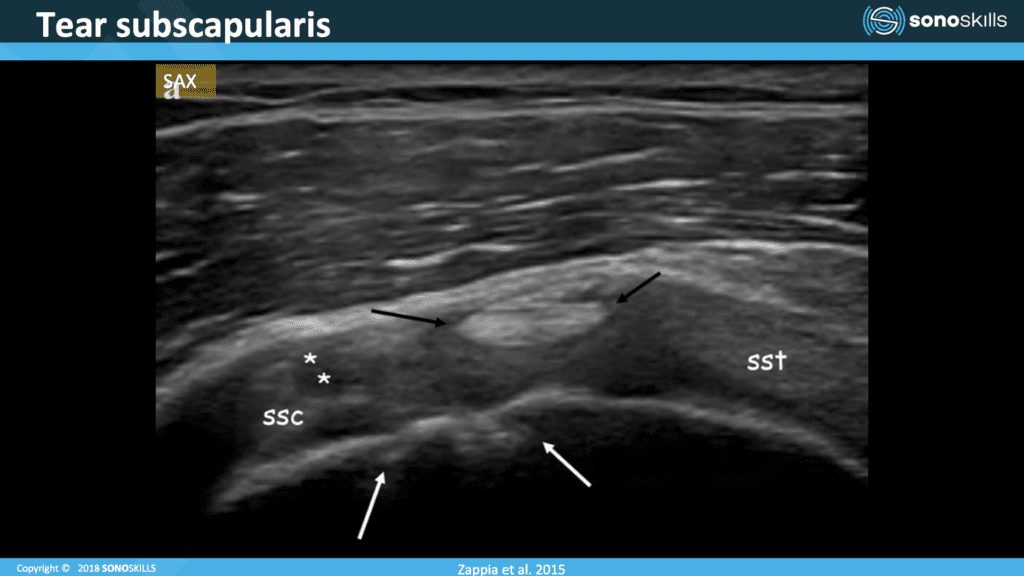

Pathology: Tear Subscapularis

In this image, we can see that the biceps is quite high in the rotate interval. Usually it has an oblique position, one tip close to the bone. The other side is a little bit on top of the superior glenohumeral ligament, but in this case, we can see the biceps is high. There is a tearing of the coracohumeral ligament. We can see chondral print sign, a sign of instability and we can also observe that this part of the subscapularis has been torn.